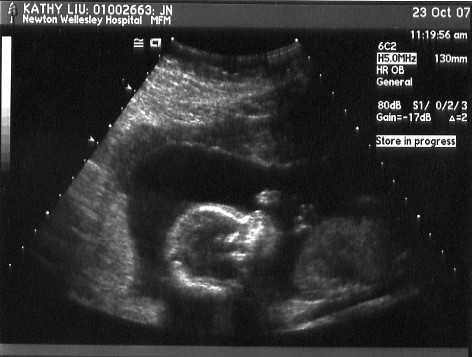

Don't know why, but it looks like she's slid all the way over to one side here!